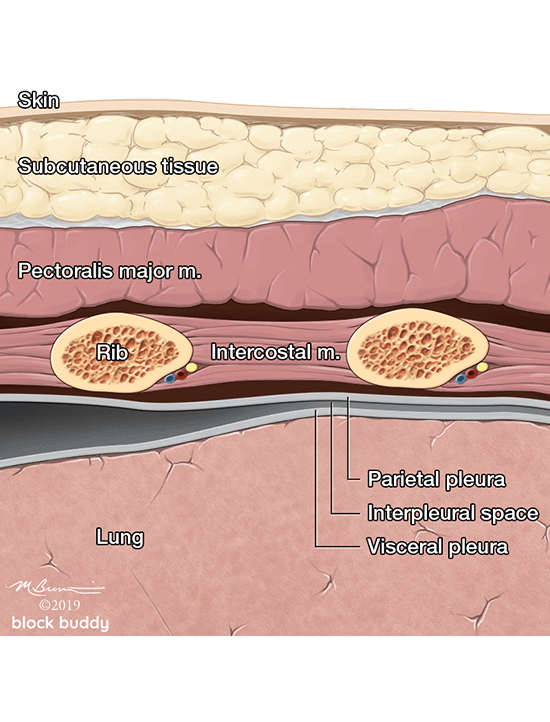

3. Anatomy

Anatomy

- The ribs will appear as convex hyperechoic lines with acoustic shadows.

- Located between the ribs are the hypoechoic intercostal muscles and the smooth, thin hyperechoic pleural line.

- These structures form the “bat sign”: the shadow of the ribs form the wings, while the area between the ribs represents the body.

- The pleural line is comprised of the parietal and visceral pleura, but will appear as a single, thin hyperechoic line.

- During normal respiration, horizontal lung sliding occurs as the parietal and visceral pleura slide in opposition.

- The pleural line between the ribs will appear to move or shimmer.